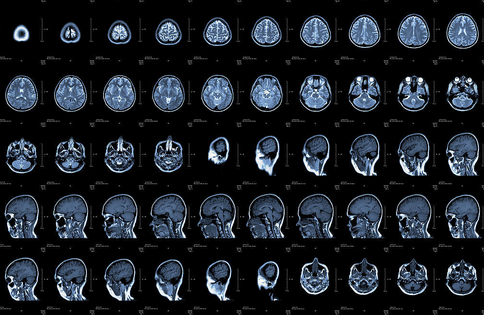

X光、CT、B超、核磁共振有什么区别

X光、CT、B超、核磁共振……这些都是医疗中常用的影像学检查法,但是它们有什么区别,看什么病应该照什么影像呢?

CT:像把面包切片看。CT是基于X光分层穿过人体,再经过电脑计算后二次成像,就像把面包切成片来看。优点是经计算后可以分层看,能显示出更多的组织信息。如果需要进一步观察骨头外伤,可以选择CT。

核磁共振:摇一摇再看。简单说就相当于摇一摇,让身体里的水分子振动起来,再平静下来,通过里面的振动来判断病灶。检查颈椎腰椎时,最佳选择是核磁共振。关节、肌肉、脂肪组织检查也可首选核磁共振。